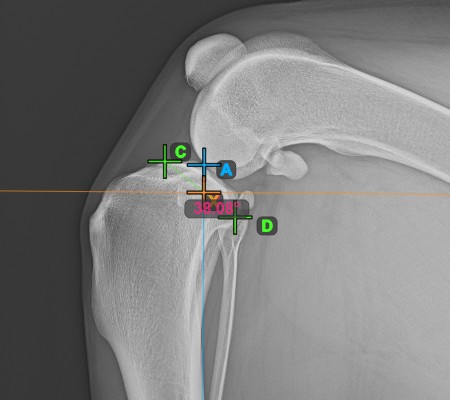

Once the long axis of the tibia has been identified, mark the most cranial point of the tibial head (tibial plateau).

The image below depicts the usual placement of the most cranial point on the tibial plateau.

Complete the TPA Angle by marking the most caudal point of the tibial head (tibial plateau). The TPA Angle is automatically calculated as the angle between the line connecting the two points on the tibial plateau and the perpendicular line to the long axis of the tibia.

The image below depicts the usual placement of the most caudal point on the tibial plateau and the automatically calculated TPA Angle measurement.